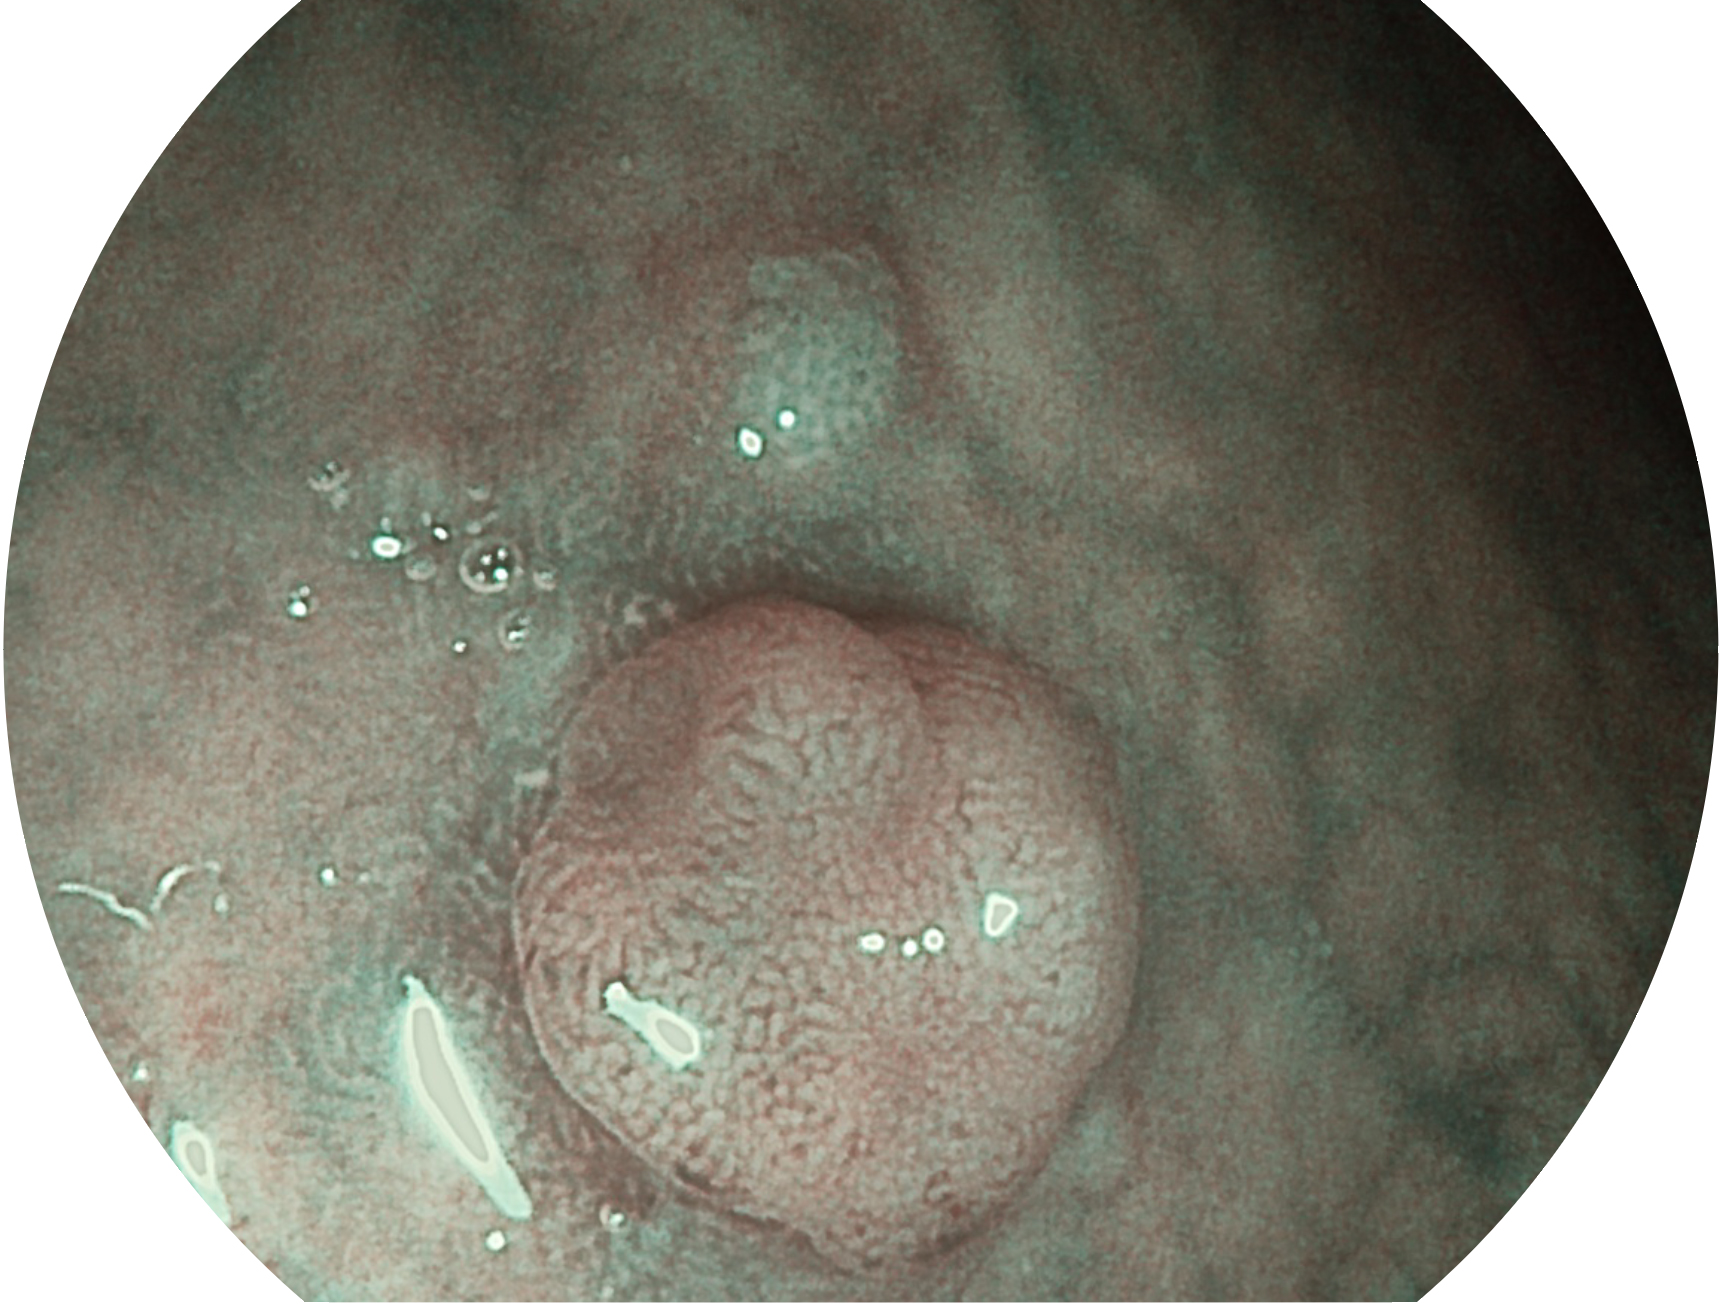

開立新開發(fā)的內(nèi)鏡染色技術(shù),主要是基于多波長LED 光源的開發(fā),VLS-55Q 四波長LED 光源是由四個不同顏色的LED光按照相應(yīng)照明模式所規(guī)定的特定發(fā)光比例進(jìn)行合束后形成,合束后形成的照明光的光譜由紅光、綠光、藍(lán)光及藍(lán)紫光這四個不同的波段范圍構(gòu)成。具有更高光譜自由度,通過光譜比例的控制,實現(xiàn)了聚譜成像技術(shù),英文全稱為“Spectral Focused Imaging, SFI”,縮寫為“SFI”和光電復(fù)合染色成像技術(shù),英文全稱為“Versatile Intelligent Staining Technology, VIST”,縮寫為“VIST”。